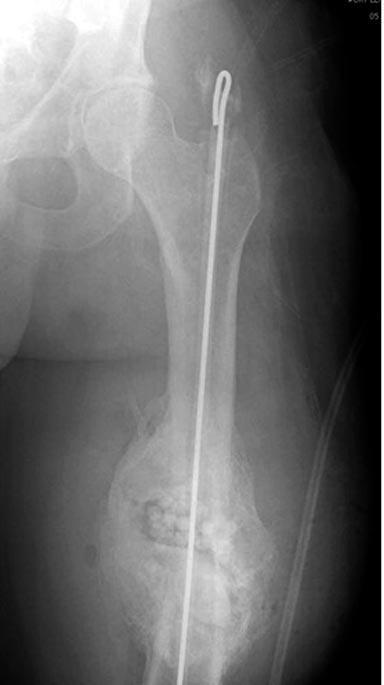

На снимках осложнение огнестрельного перелома бедра поздней инфекцией. 7 лет назад оперирован: правое бедро, сперва на ExFix, затем заменен на гвоздь, а левая - гвоздь при поступлении.

Беспокойство проявил недавно, по поводу жалоб на боли сделано МРТ и дренирование абсцесса терапевтами. Мы удалили гвоздь, сделали I&D, рассверливание канала, и ввели гвоздь с антибиотиком. Для гвоздя использовали стерильную трубку-форму, а антибиотик по 1.0 Tobramycin c Vancomycin.

В замкнутом без перелома пространстве во время риминга повышается давление внутри канала, и имеется риск тромбообразования. Для профилактики и для дренажа - каннюлированный винт 6.5 мм в дистальной части бедра. Обработку заканчивают культурой из раны и канала. Иногда процедуру надо будет повторить.

Рекомендуется: антибиотический гвоздь на цементе. Нагрузку можно разрешить сразу, перелом сросся давно!

Гвозди с антибиотиком все custom made, т.е. делаются во время операции. Диаметр зависит от внутреннего диаметра канала. Обычно достаточным бывает 10 мм, и редко применяется готовые гвозди для армирования цемента. Трубка в 10 мм для плевральной полости как форма и армирование 2.8 или 3.2 мм guide wire для гвоздей, которая срезается по длине, на конце делается петля для облегчения удаления.

В представленном случае, из-за большого диаметра первичного гвоздя (13мм) применили готовый гвоздь в 11 мм, а трубка с внутренним диаметром 16 мм.

Здесь представлены примеры подготовки гвоздя....